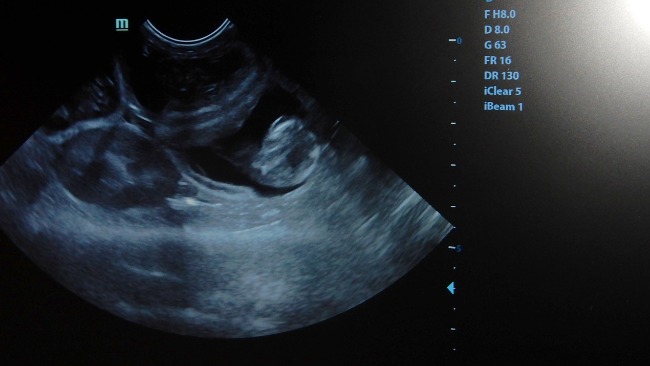

W przerwie między pacjentami dokładniejsze badanie - urwany i oskórowany - dość niedawno - ogonek widać gołym okiem, usg - ciąża, 4-5 płodów...